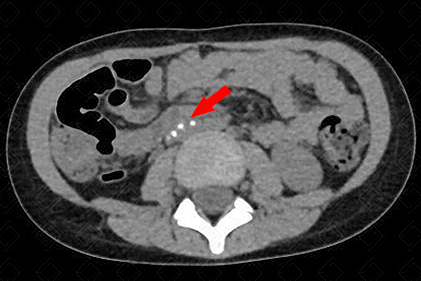

Texto alternativo para a imagem Figura 2. Créditos: Dra. Elazir Mota - Rio de Janeiro/RJ

Descrição das figuras 1 e 2: Tomografia computadorizada do abdome nas fases portal (esquerda) e excretora (direita) evidenciando falha de enchimento na topografia do cálice menor e pirâmide, com preenchimento periférico do contraste (seta vermelha), por necrose papilar.

• Urotomografia: A pesar da radiação ionizante, tem sido um exame cada vez mais utilizado para confirmar este diagnóstico. Observaremos um cálice convexo com extravasamento de contraste para a papila renal, na maioria dos casos (f iguras 1 e 2) . No caso apresentado, tratava-se de paciente com tuberculose - observe os linfonodos calcificados no mesentério (f igura 3) .